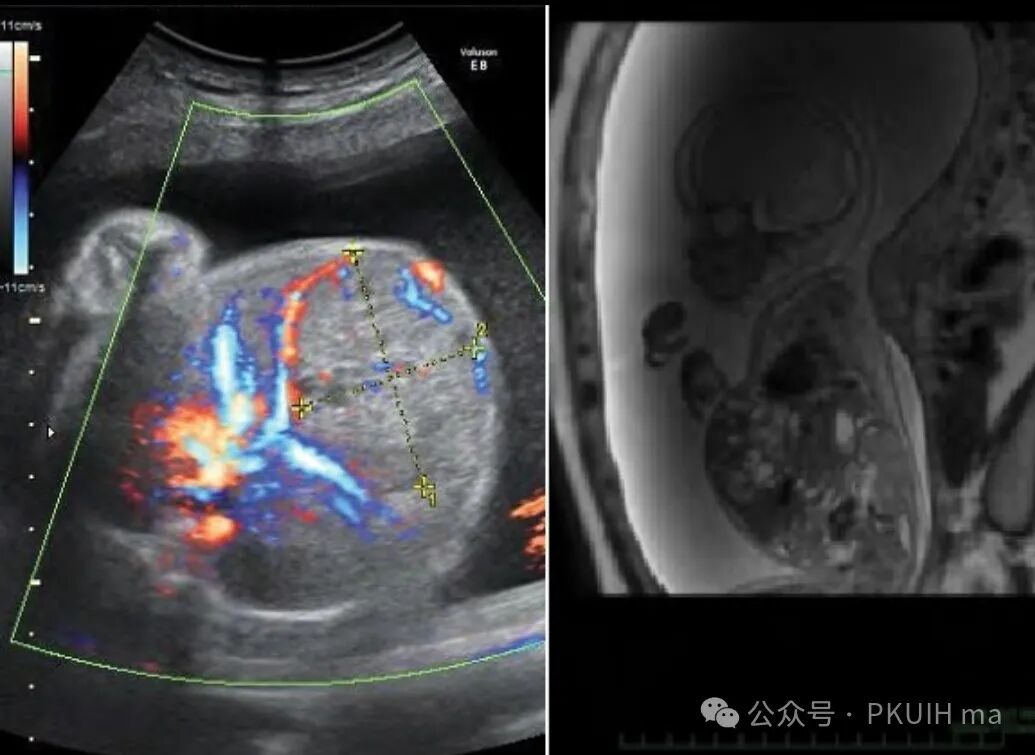

上图是中孕期发现的肝脏占位,随后做了核磁怀疑肝母。